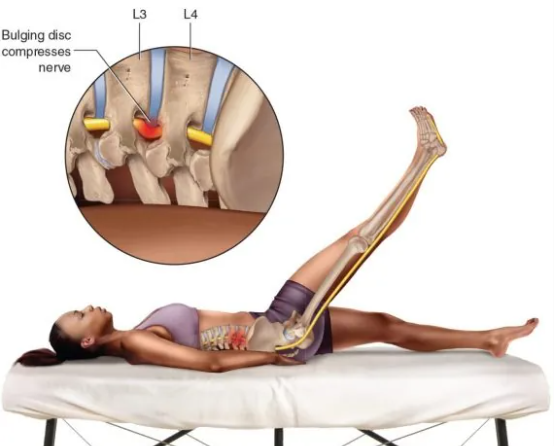

EL SIGNO DE LASÈGUE El signo de Lasègue es una prueba clínica neurológica utilizada para evaluar irritación o compresión del nervio ciático, generalmente por hernia discal lumbar. ¿CÓMO SE REALIZA? El paciente está en decúbito supino. El examinador eleva pasivamente...